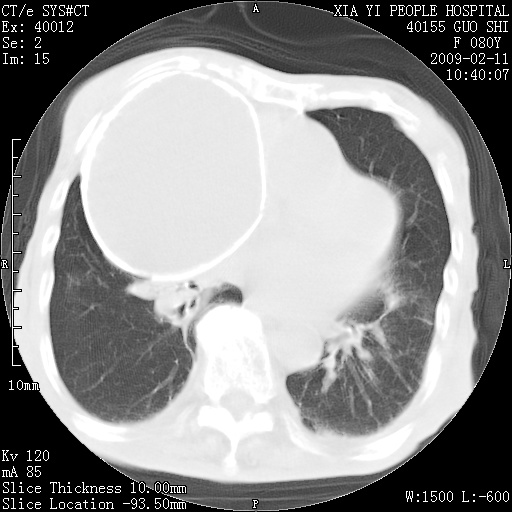

以下是引用随光逐影在2009-2-16 16:34:00的发言:[br]1)考虑右前纵隔皮样囊肿。2)双侧少量胸腔积液。

以下是引用zjzjr在2009-2-16 17:30:00的发言:[br]支持囊性畸胎瘤 双侧少量胸腔积液。